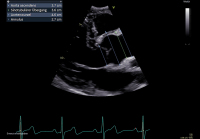

Aortenklappeninsuffizienz: Was gibt es Neues? // Aortic valve regurgitation – What do the 2021 guidelines say? What has changed from 2017?

Journal für Kardiologie - Austrian Journal of Cardiology 2024; 31 (5-6): 120-128 Volltext (PDF) Summary Abbildungen